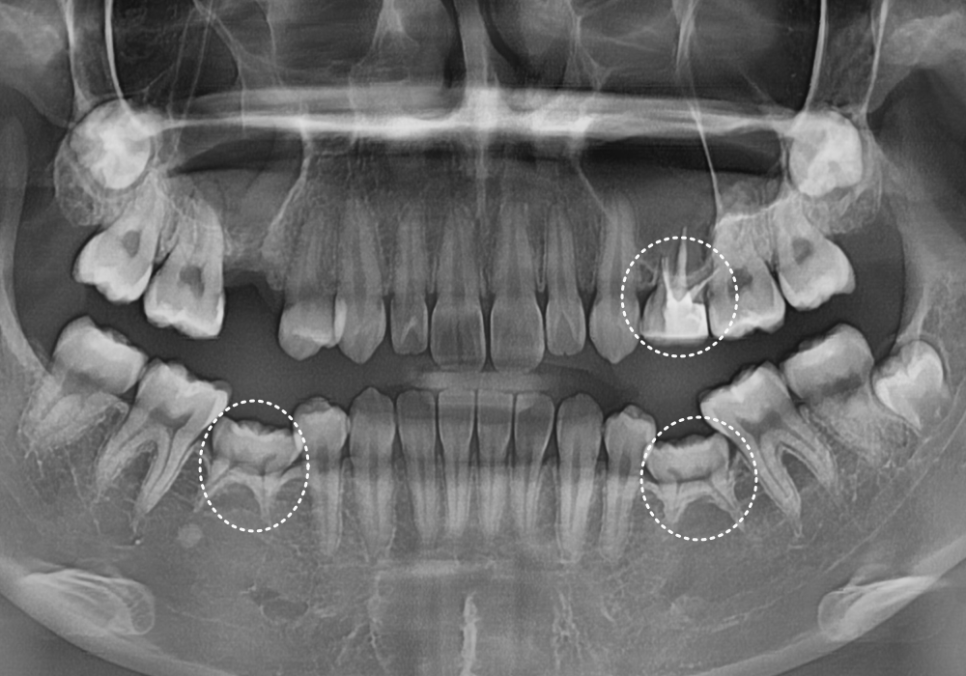

최근 저희 치과를 찾으신 20대 환자분은

위아래, 양쪽 작은 어금니가

선천적으로 결손되어 유치를

지금까지 사용하고 계셨습니다.

240308

하지만 유치의 한계로 인해

이미 오른쪽 위 유치(#55)는

충치가 심해져 잇몸뼈가 많이 녹은 상태로

발치를 진행하셨고,

왼쪽 위 유치(#65) 도 신경치료만 된 채

크라운 보호 없이 아슬아슬하게 버티고 있었죠.

임플란트를 심기 위해 오른쪽 위 잇몸뼈 상태를

CT로 확인해 보니,,

240329

남아있는 뼈의 높이가

고작 1.1mm 정도밖에 되지 않았습니다.

일반적으로 안전하게 임플란트를 심으려면

적어도 8~10mm 정도의 뼈 높이가 필요해요.

그런데 1.1mm라는 수치는

사실상 뼈가 거의 없는 종잇장처럼

아주 얇은 상태라고 볼 수 있거든요.